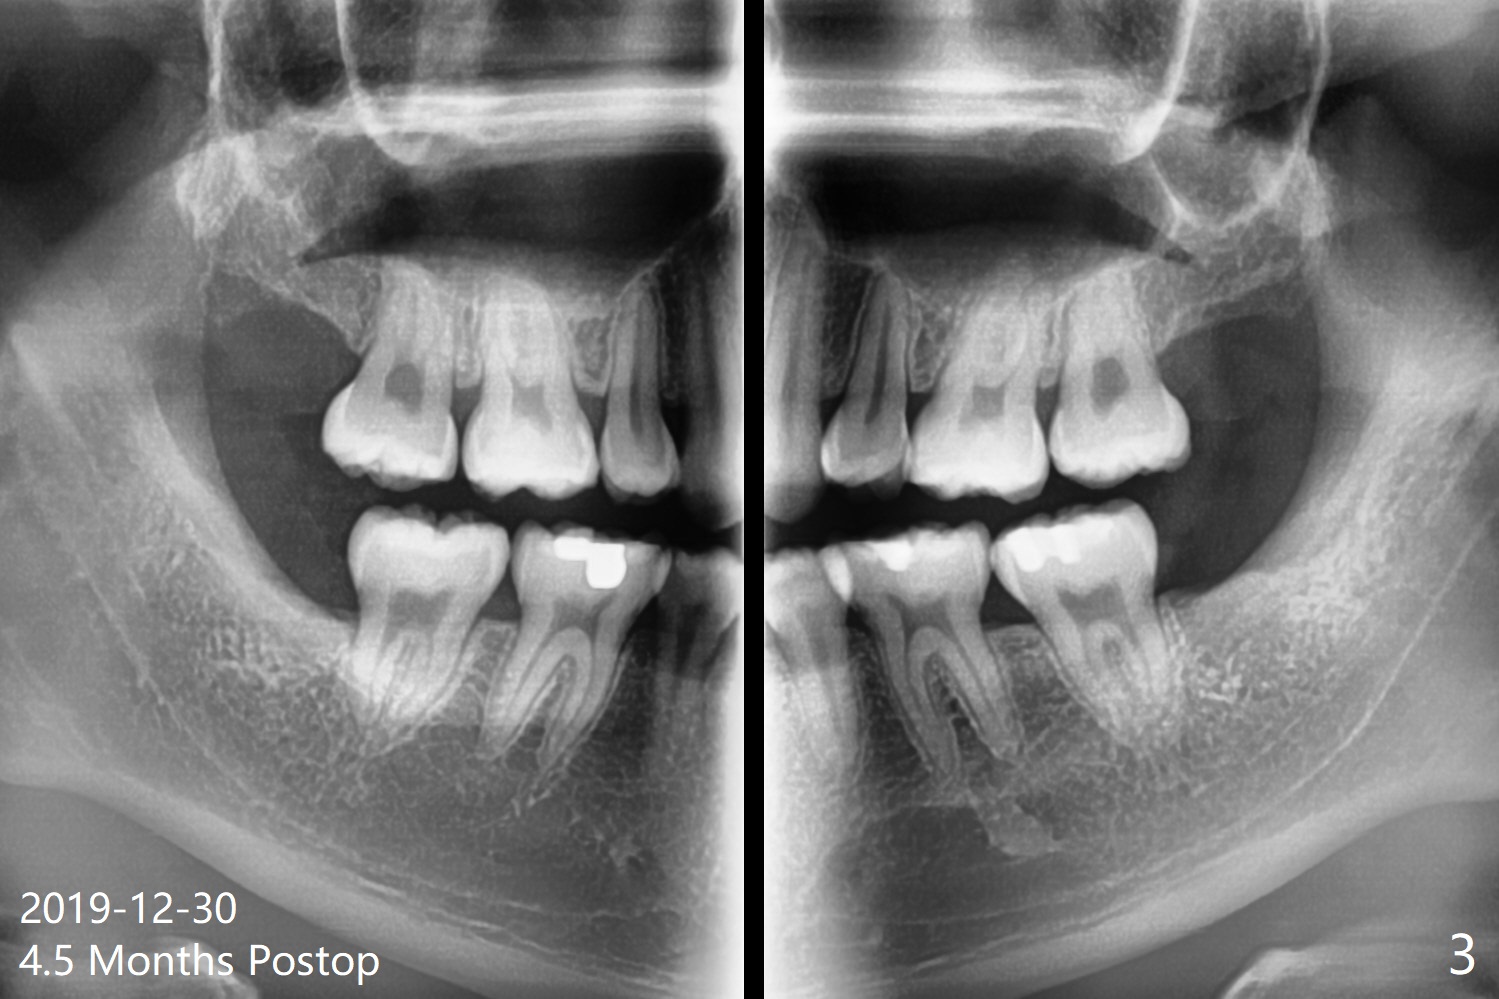

A 19-year-old man with history of orthodontic treatment (Fig.1,2) returns to office for #1,16,17,32 extraction with Collagen Plug placement at #17 and 32 (4-0 plain gut suture). The sockets heal in 4.5 months (Fig.3).